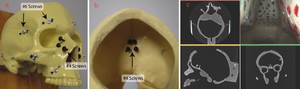

Publication: J Craniomaxillofac Surg. 2016 Feb;44(2):202-9. PMID: 26748414 Authors: Szymor P, Kozakiewicz M, Olszewski R. Institution: Department of Maxillofacial Surgery, Medical University of Lodz, Lodz, Poland. Background/Purpose: In this study, we aimed to verify the accuracy of models created with the help of open-source 3D Slicer 3.6.3 software (Surgical Planning Lab, Harvard Medical School, Harvard University, Boston, MA, USA) and the Mcor Matrix 300 paper-based 3D printer. Our study focused on the accuracy of recreating the walls of the right orbit of a cadaveric skull. Cone beam computed tomography (CBCT) of the skull was performed (0.25-mm pixel size, 0.5-mm slice thickness). Acquired DICOM data were imported into 3D Slicer 3.6.3 software, where segmentation was performed. A virtual model was created and saved as an .STL file and imported into Netfabb Studio professional 4.9.5 software. Three different virtual models were created by cutting the original file along three different planes (coronal, sagittal, and axial). All models were printed with a Selective Deposition Lamination Technology Matrix 300 3D printer using 80 gsm A4 paper. The models were printed so that their cutting plane was parallel to the paper sheets creating the model. Each model (coronal, sagittal, and axial) consisted of three separate parts (∼200 sheets of paper each) that were glued together to form a final model. The skull and created models were scanned with a three-dimensional (3D) optical scanner (Breuckmann smart SCAN) and were saved as .STL files. Comparisons of the orbital walls of the skull, the virtual model, and each of the three paper models were carried out with GOM Inspect 7.5SR1 software. Deviations measured between the models analysed were presented in the form of a colour-labelled map and covered with an evenly distributed network of points automatically generated by the software. An average of 804.43 ± 19.39 points for each measurement was created. Differences measured in each point were exported as a .csv file. The results were statistically analysed using Statistica 10, with statistical significance set at p < 0.05. The average number of points created on models for each measurement was 804.43 ± 19.39; however, deviation in some of the generated points could not be calculated, and those points were excluded from further calculations. From 94% to 99% of the measured absolute deviations were <1 mm. The mean absolute deviation between the skull and virtual model was 0.15 ± 0.11 mm, between the virtual and printed models was 0.15 ± 0.12 mm, and between the skull and printed models was 0.24 ± 0.21 mm. Using the optical scanner and specialized inspection software for measurements of accuracy of the created parts is recommended, as it allows one not only to measure 2-dimensional distances between anatomical points but also to perform more clinically suitable comparisons of whole surfaces. However, it requires specialized software and a very accurate scanner in order to be useful. Threshold-based, manually corrected segmentation of orbital walls performed with 3D Slicer software is accurate enough to be used for creating a virtual model of the orbit. The accuracy of the paper-based Mcor Matrix 300 3D printer is comparable to those of other commonly used 3-dimensional printers and allows one to create precise anatomical models for clinical use. The method of dividing the model into smaller parts and sticking them together seems to be quite accurate, although we recommend it only for creating small, solid models with as few parts as possible to minimize shift associated with gluing. |